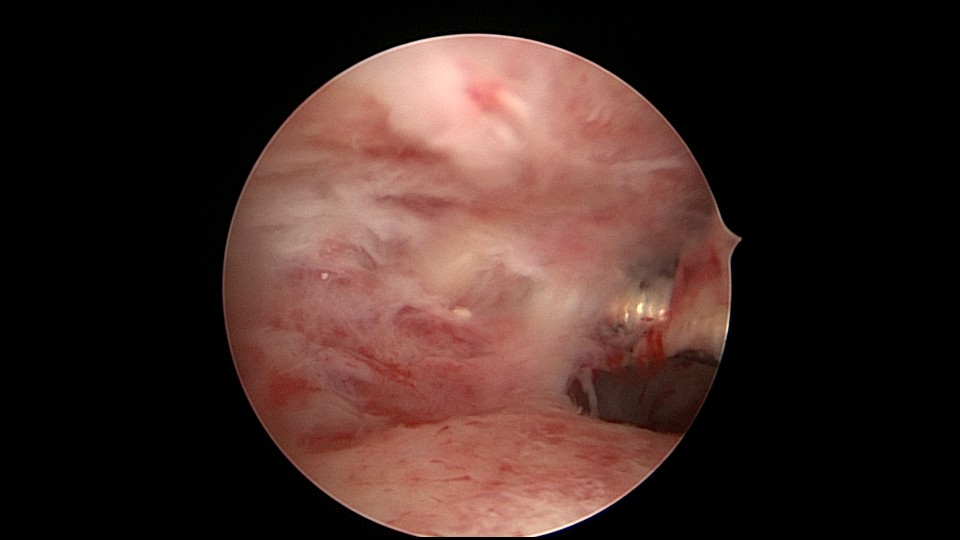

患者51岁,G4P3,顺产3次,闭经半年,外院B超提示有2个环。反复追问病史,还原宫内双环情况,24年前最后一次妊娠可能为带环受孕,行人流术,环未取出(医生和病人不知道有环),随即再次放环一枚。宫腔镜见母体乐环位置下移,纵臂卡在宫颈管内,宫腔镜难以进入宫腔,异物钳先取出母体乐。宫腔内见另一O型环,与右侧宫壁广泛嵌顿,异物钳、取环钩配合中弯钳拉出节育环,环完整,扭曲变形,宫壁见节育环割裂痕迹,宫腔无其他异常。